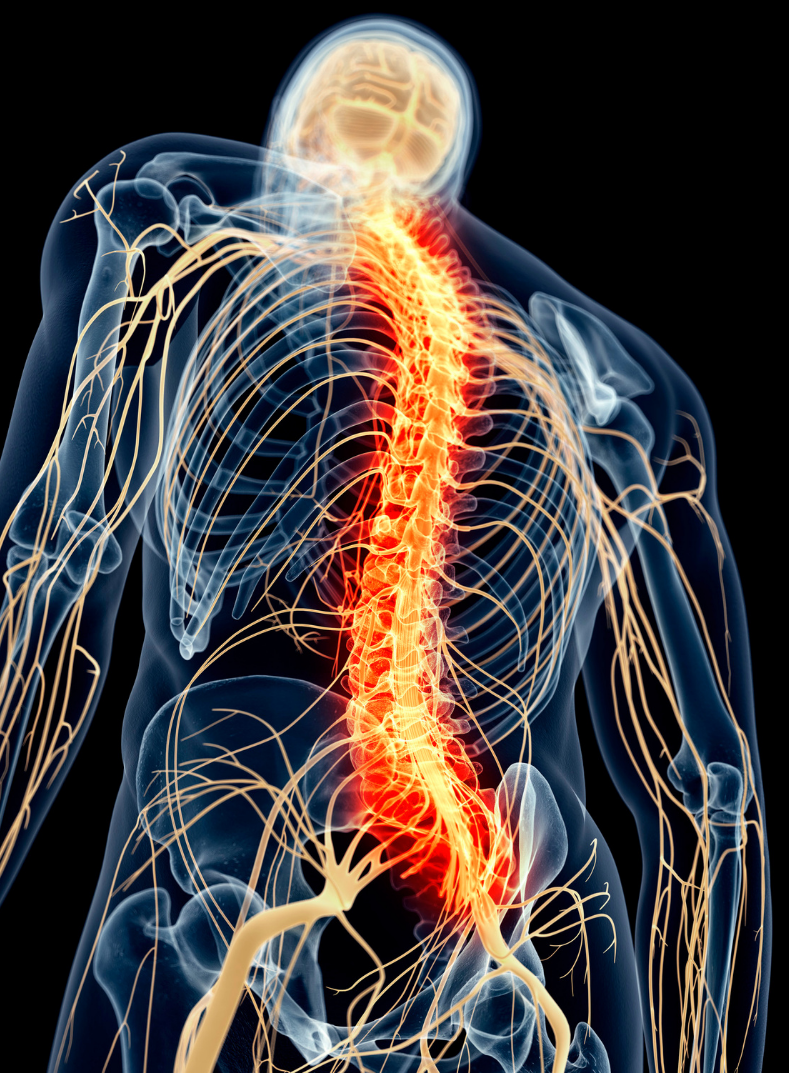

La moelle épinière est la partie du système nerveux central qui se situe à l’intérieur de la colonne vertébrale. Il s’agit d’une structure essentielle aux sensations en provenance de notre corps et aux fonctions motrices.

Lésion Médullaire

Une lésion à la moelle épinière, ou lésion médullaire, coupe la communication entre le cerveau et le corps et entraîne la paralysie totale ou partielle des membres et du tronc.

L'étendue de la paralysie dépend de la localisation de la lésion dans la colonne vertébrale et de sa gravité.